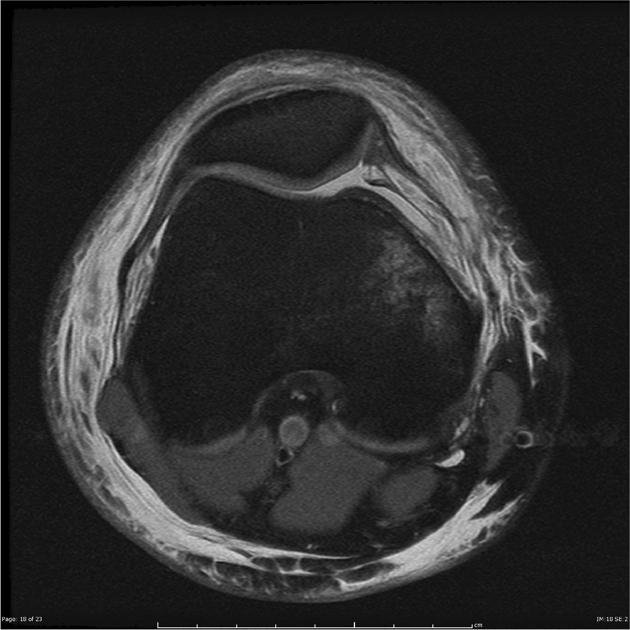

MRI (Magnetic Resonance Imaging)

- An MRI scan is the most useful test for visualising the MPFL and other soft tissues.

- It can show whether the MPFL is torn, stretched, or scarred, and whether there is associated cartilage or bone damage.

- MRI can also identify risk factors for ongoing instability, such as trochlear dysplasia or patella alta.